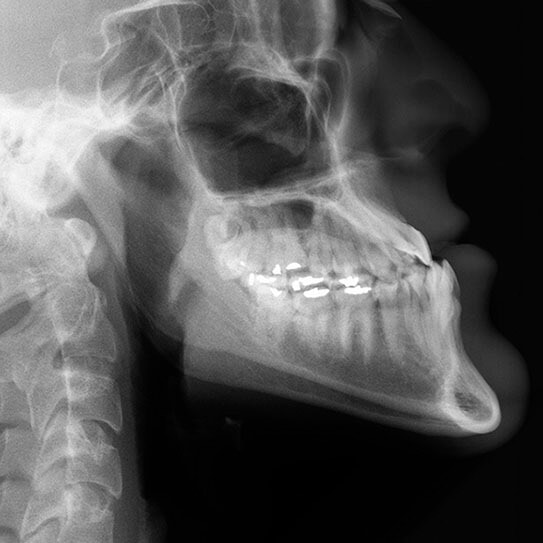

Types of Malocclusions

OUR TEETH ARE MEANT to fit together in a specific way. It’s how we are able to chew effectively and speak clearly. When the upper and lower teeth don’t fit together the way they should, we call that a malocclusion, or bad bite. In addition to impeding those important functions, a malocclusion can also result in jaw problems, put teeth at risk of breaking, and even make digestion less efficient.

When the jaw is closed in a healthy bite, the upper teeth should rest slightly over the lower teeth, and the points of the upper molars should fit into the grooves of the lower molars. Let’s go over five of the most common ways a bite can veer off of what is healthy.

• Excessive overbite: the upper teeth overlap or overjet the lower teeth by too much for a healthy bite.

• Deep bite: such a severe overbite that the upper front teeth completely overlap the lower front teeth, which may even drive into the gums behind the upper teeth, risking injury to the gum tissue.

• Open bite: sometimes the result of a tongue thrust habit or aggressive thumbsucking in the preschool years and beyond, the upper front teeth flare out, leaving a gap between them and their lower counterparts when biting down.

• Crossbite: when the jaw is closed, some upper teeth are on the outside and some lower teeth are on the outside.

• Underbite: when the jaw is closed, the lower teeth jut out in front of the upper teeth.